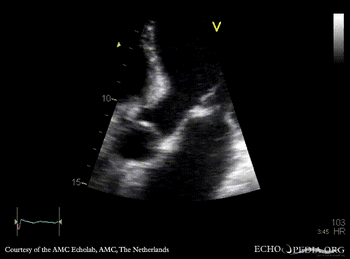

Endocarditis of mitral valve

A3CH: vegetations on AMVL A2CH